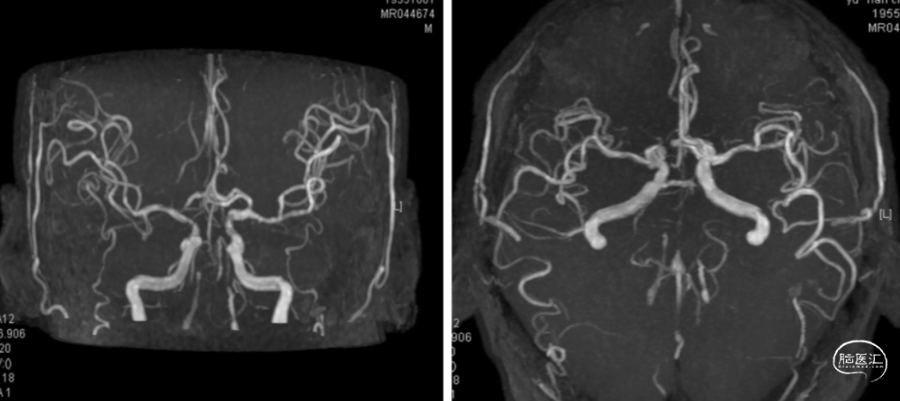

颈内动脉造影:

正位

侧位

右椎动脉造影: